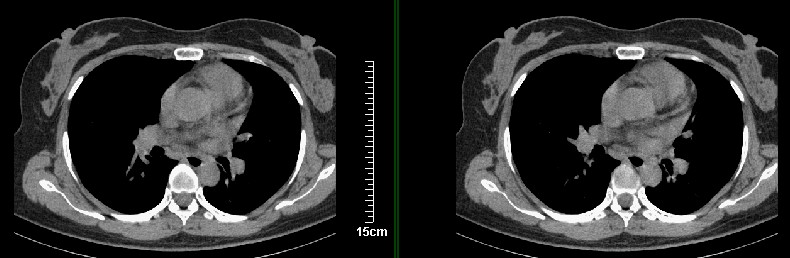

一周之后 复查结果 5mm扫描 40多岁 我们医院的护士

病灶分明小多多了